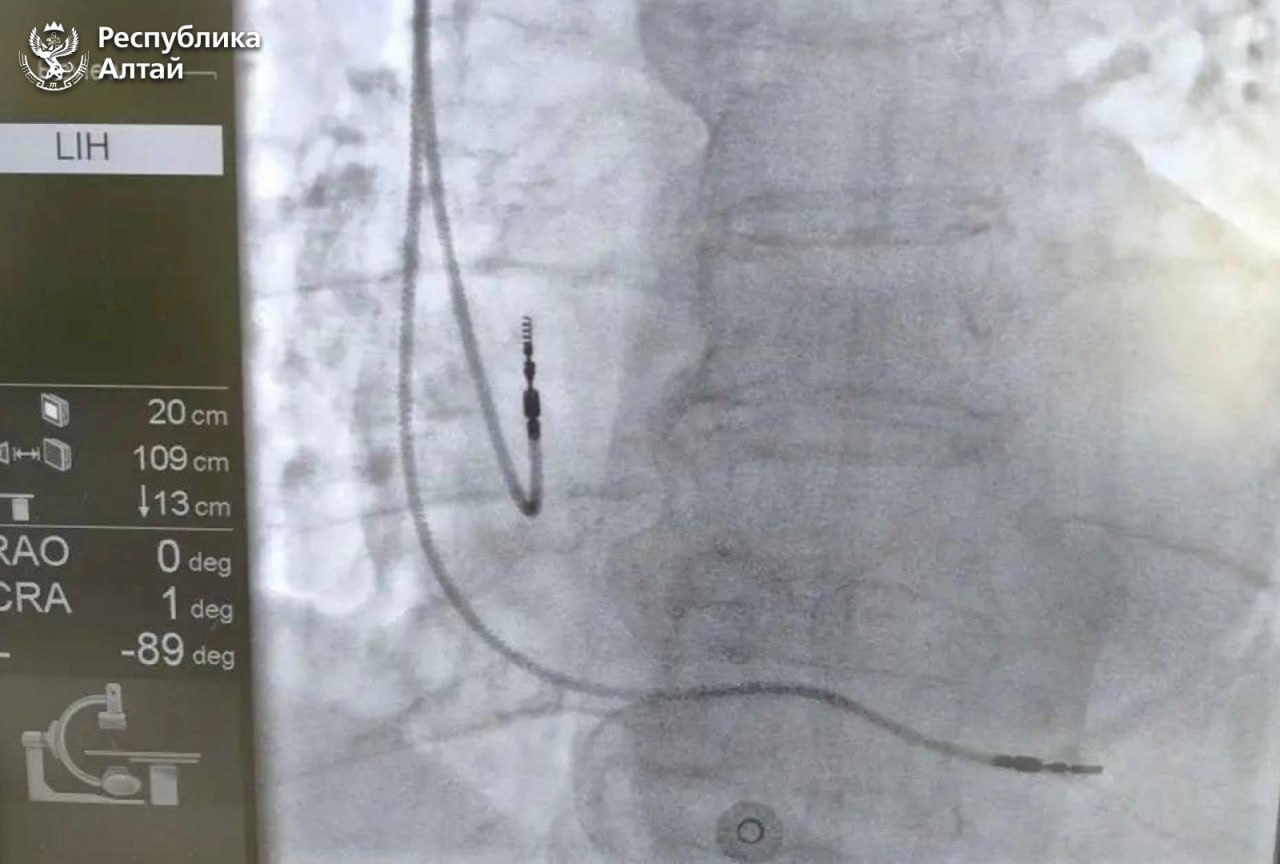

В Республиканской больнице впервые начали проводить операции по установке кардиостимуляторов. Об этом сообщил глава региона Андрей Турчак.

По его словам, это особенно актуально для пациентов с пониженным пульсом, а также блокадами и аритмиями, угрожающими жизни.